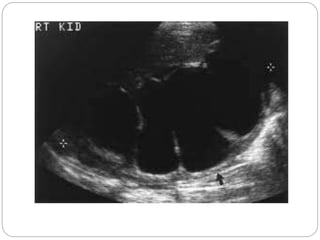

Parapelvic cyst

Severe hydronephrosis with

proximal hydro ureter

Moderate hydronephrosis on

right and severe on left